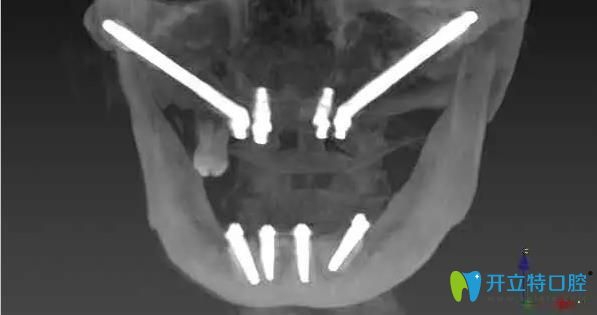

林阿姨,68歲,上下牙缺失多年,牙槽骨大量缺失,上頜竇氣化非常嚴(yán)重,前牙區(qū)的骨骼也特別窄、矮,做任何的修復(fù)都很困難,所以陳慧玲院長建議她做穿顴骨種植。

陳慧玲院長經(jīng)過詳細(xì)的術(shù)前檢查、做了充分的種植手術(shù)評估后,確定了種植方案。在多名醫(yī)生的共同努力下,利用穿顴種植+穿翼種植技術(shù),用六顆種植體來進(jìn)行上半口全固定修復(fù),即刻種植、即刻修復(fù)。當(dāng)天下午,林阿姨就戴上了固定臨時(shí)牙,回家就可以吃東西。